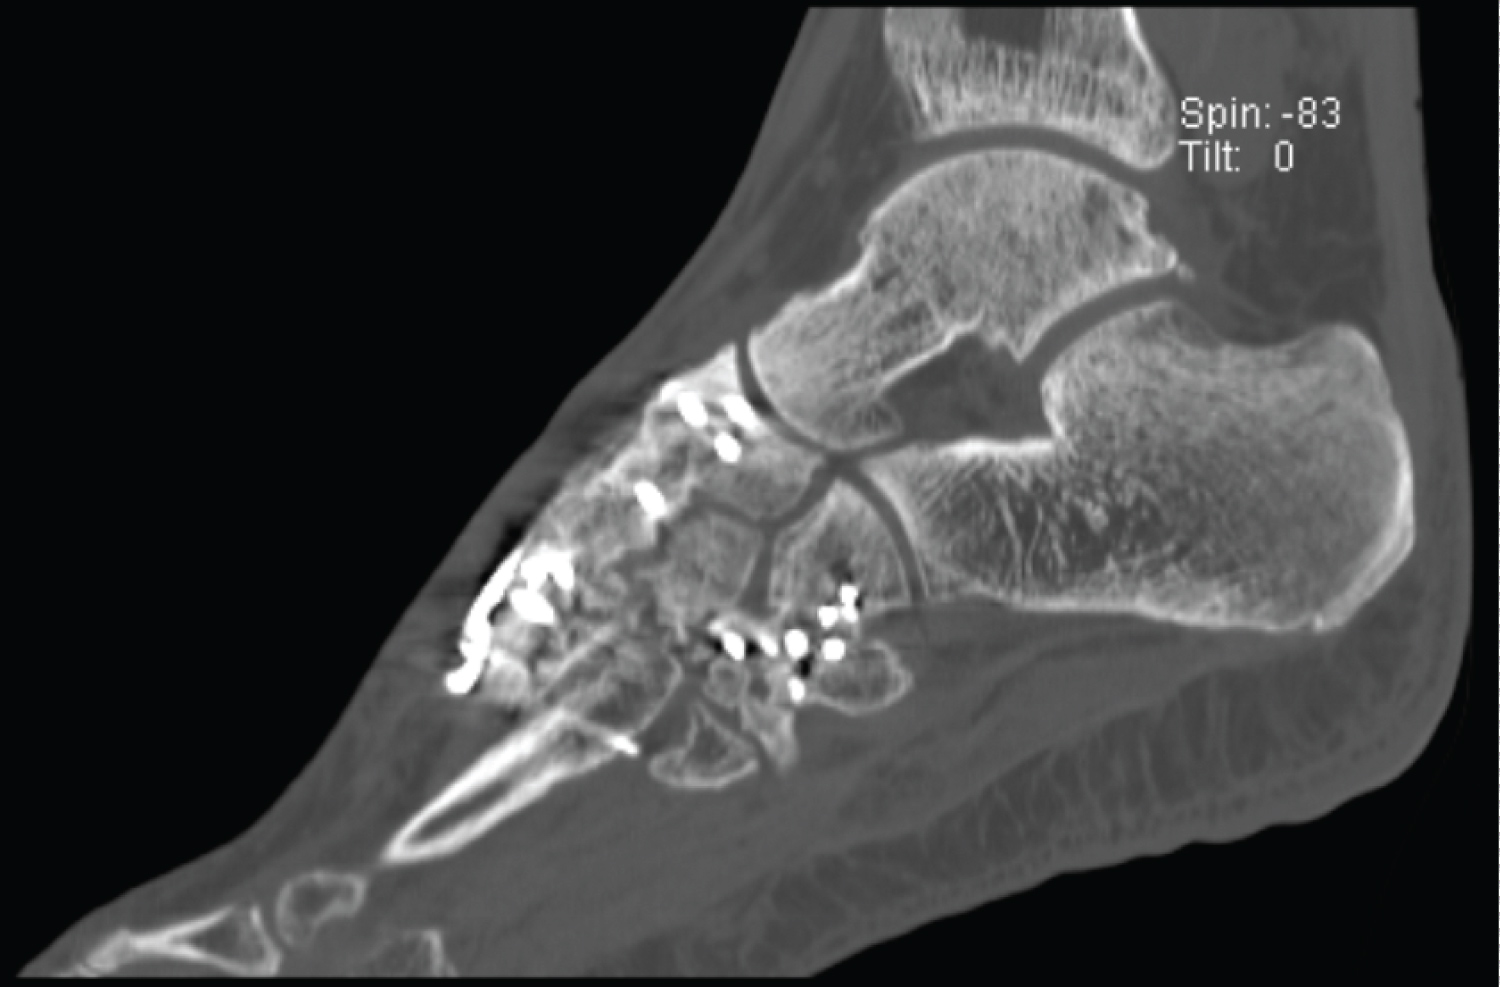

A 42-year-old patient presented himself with massive pain, swelling and weight-bearing intolerance of the left foot after a motorbike accident. Having slipped on his motorbike in a curve, the motorbike had fallen directly on his left foot. X-rays taken in the ER already showed a Lisfranc dislocation fracture. A CT-scan was subsequently performed to assess the fracture, whereby multifragmentary, intra-articular comminuted fractures involving all articular surfaces of the cuboid bone, intermediate cuneiform and lateral cuneiform could be revealed. The intermediate cuneiform was dorsally dislocated in relation to all adjacent articular partners. In addition, there were multi-fragmentary intra-articular base fractures of the third and fourth metatarsals and a slightly dislocated head fracture of the third metatarsal. Due to soft tissue swelling, the lower leg was primarily immobilised in a cast until the operation could be performed (Figure 2).

Figure 2: Pre-operative axialand sagittal CT-cuts show a dorsal dislocation of the intermediate cuneiform of 14 mm. View Figure 2